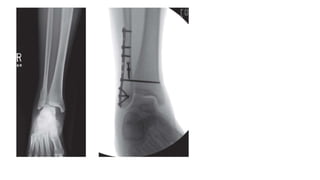

• ISOLATED LATERAL MALLEOLUS FRACTURE

 Operative (ORIF)

 Open reduction and plating

 plate placement

 lateral

 lag screw fixation with neutralization plating

 bridge plate technique

 posterior

 antiglide technique

o most common disadvantage of using posterior antiglide plating

is peroneal irritation if the plate is placed too distally

o posterior antiglide plating is biomechanically superior to lateral

plate placement

 intramedullary retrograde screw placement